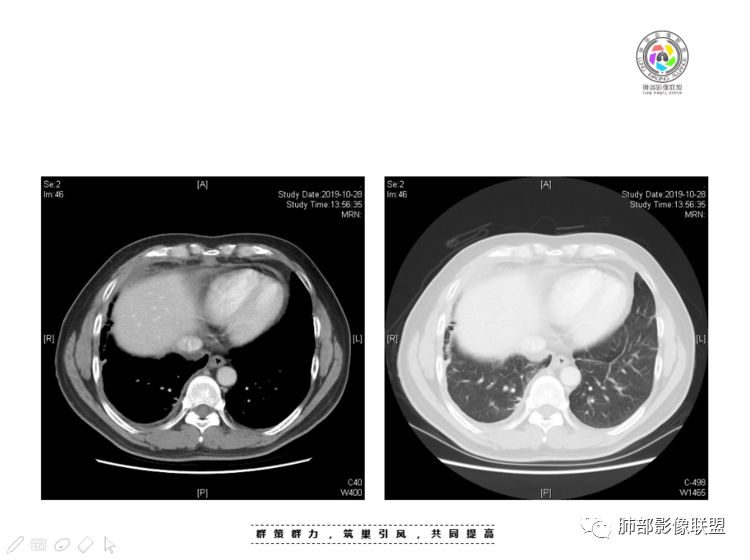

Coke with ice:囊性部分考虑包裹性积液?南边:不是积液;有间隔;张力高;而且位置有些特殊

大家仔细看看积液中的游离气体;

不是支气管,是积气;是穿刺进去的;

囊内密度不一致

我认为囊张力高,积液中的气体均在周围,外侧、下方,囊内有间隔:各腔密度不一致;提示:囊腔属于前纵隔,不是包裹性积液;现在的问题:囊腔与内侧的病灶是否是一体的

2、前纵隔内病灶囊实性混杂密度病灶,囊性病灶主要位于右侧,张力较高,有分隔影,囊壁右侧缘光整,病灶左侧实性部分边界不清明显强化,病灶肺瘤交界面大部分边界清楚,部分模糊。